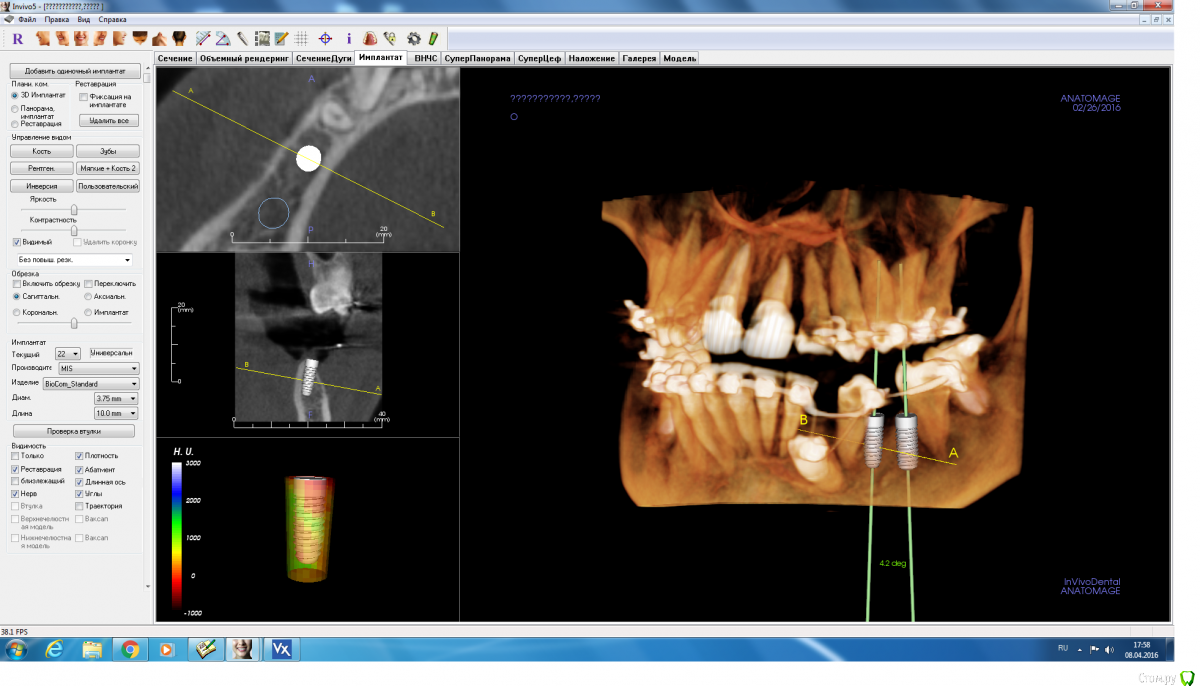

adamskot Опубликовано 8 апреля, 2016 Автор Поделиться Опубликовано 8 апреля, 2016 а как поступили бы Вы?)расщепление с постановкой 3.75 - 10 и 4.2 - 10, аутокостью + биоосс и мембраной... Ссылка на комментарий

IvanK Опубликовано 8 апреля, 2016 Поделиться Опубликовано 8 апреля, 2016 я бы поставил два имплантата анкилос линейки А + сст Ссылка на комментарий

adamskot Опубликовано 8 апреля, 2016 Автор Поделиться Опубликовано 8 апреля, 2016 я бы поставил два имплантата анкилос линейки А + сств распоряжении есть мис и нобель, то есть постановка винтов с миксом из кости и "соседжом"? Ссылка на комментарий

red_butler Опубликовано 8 апреля, 2016 Поделиться Опубликовано 8 апреля, 2016 в распоряжении есть мис и нобельсюда с коническим соединением просятся, и заглубить Ссылка на комментарий